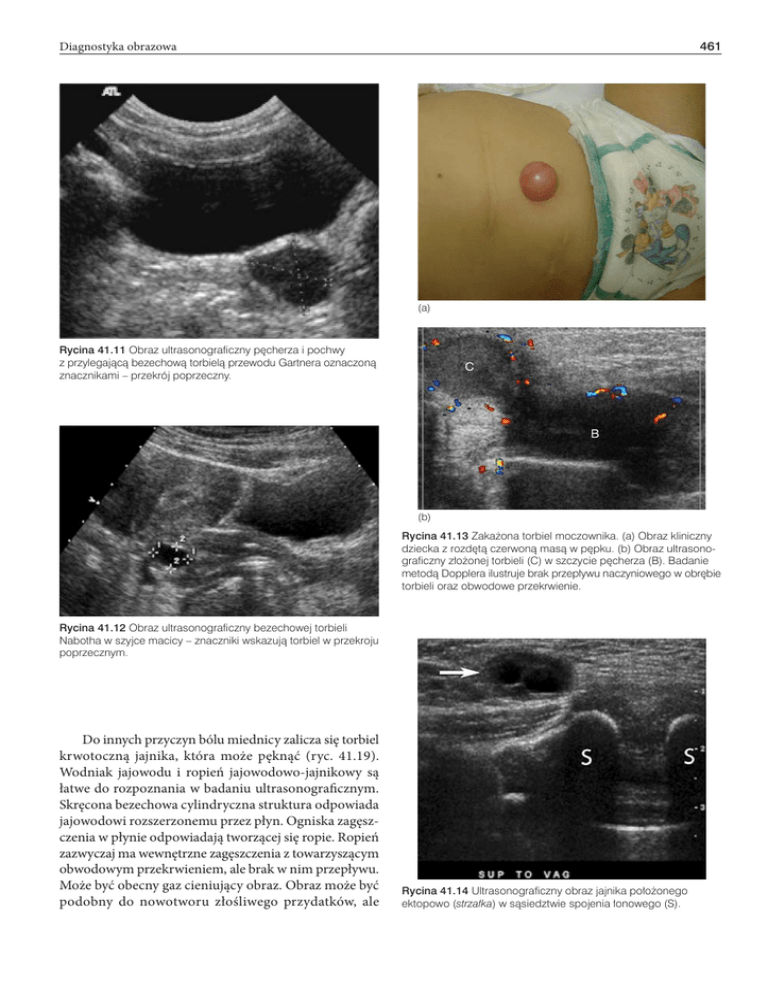

Rycina 41.14 Ultrasonograficzny obraz jajnika położonego

ektopowo (strzałka) w sąsiedztwie spojenia łonowego (S).